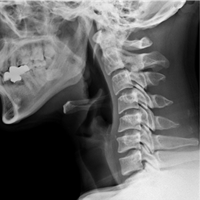

• Flat Neck

(Loss of C-curve)

on X-ray

• Forward Head Posture

(Reverse C-curve)